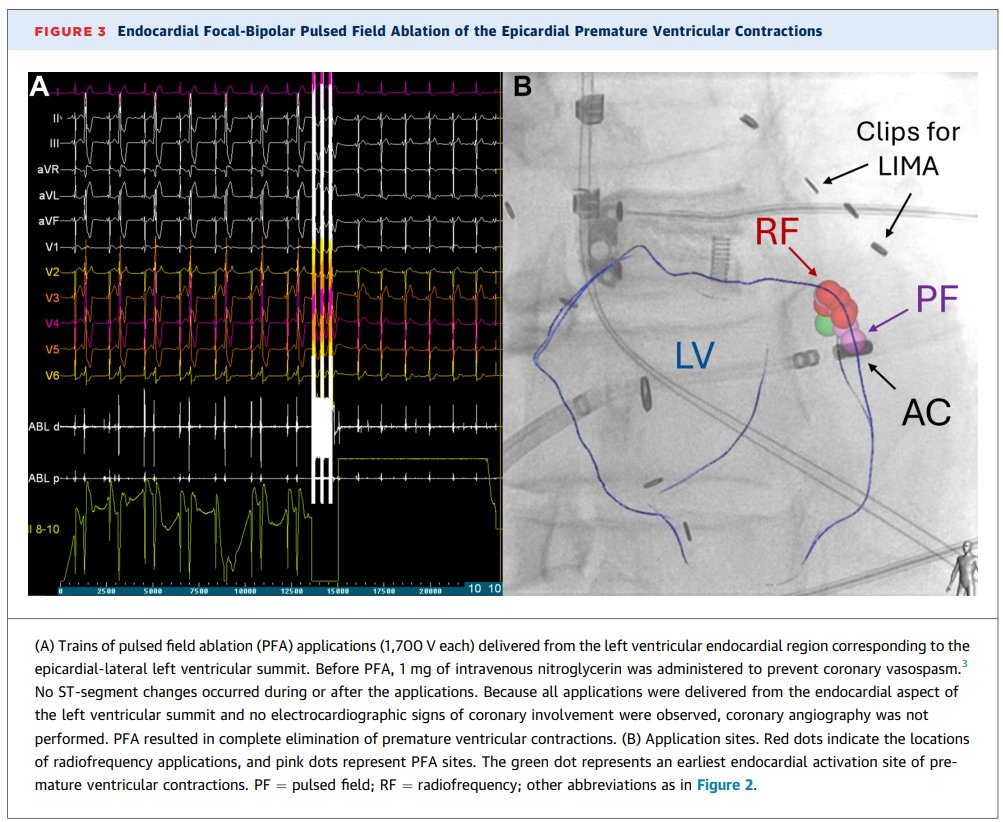

Endocardial pulsed field ablation of an inaccessible epicardial LV summit PVC 81-yo post-CABG patient → RF failed, no veins for alcohol, epicardial access impossible Focal-bipolar PFA from inside the LV → instant PVC termination + full transmural scar on MRI + 100% PVC-free

Have you ever tackled a tough RVOT PVC case with an abrupt precordial transition zone in V4? Focal-bipolar pulsed field ablation (PFA) can work in the infundibular zone of the anteromedial RVOT. Anatomical image courtesy Prof. Kalyanam Shivkumar (Amara-Yad Project).